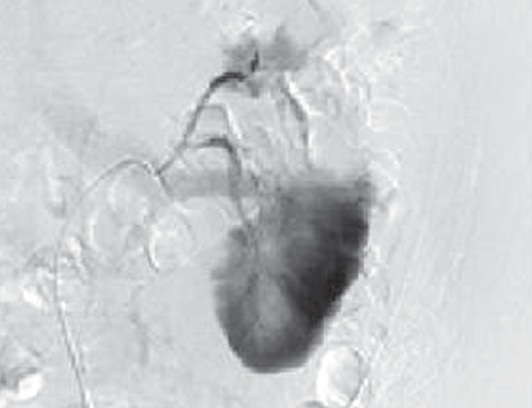

На 2-е сутки послеоперационного периода зафиксировано поступление по дренажу геморрагического отделяемого в объеме 400 мл. Пациенту экстренно выполнена ангиография левой почечной артерии. Выявлена экстравазация контрастного вещества через культю верхней сегментарной артерии почки (рис. 4). Осуществлена селективная эмболизация верхней сегментарной артерии (рис. 5). После эмболизации наблюдалось постепенное уменьшение отделяемого по дренажу до 30 мл. На 7-е сутки после операции отмечено поступление по дренажу около 500 мл светло-желтого отделяемого, при биохимическом анализе которого содержание мочевины составило 12,8 ммоль/л, креатинина 488 ммоль/л, что указывало на формирование мочевого свища. Пациенту выполнены цистоскопия и ретроградная уретеропиелография. Выявлена экстравазация контрастного вещества через верхнюю группу чашечек. Произведено стентирование левого мочеточника двухпетлевым антирефлюксным мочеточниковым стентом Колопласт Fr 6, после чего выделение мочи по дренажу прекратилось. Дренажная трубка из забрюшинного пространства удалена на 9-е сутки после операции, и еще через 2 дня пациент выписан из стационара в удовлетворительном состоянии. Мочеточниковый стент удален через 4 недели после его установки.

Рис. 4. Ангиография левой почечной артерии. Экстравазация контрастного вещества через культю верхней сегментарной артерии

Fig. 4. Angiography of the left renal artery. Extravasation of the contrast agent through the stump of the superior segmental artery